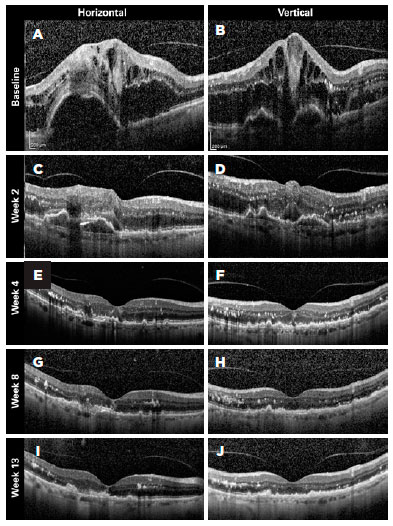

Figures 4-6 present three representative clinical cases with good treatment responses. Figure 4 presents a patient from group 1 with a large PED showing excellent response since the beginning of the treatment. Figure 5 shows the first 3 months of follow-up for a patient from group 2, who was treated every 2 weeks with fixed injections in all first six study visits and was then followed with retreatments as needed. Despite the case severity, the patient progressed with a good treatment response. Figure 6 presents a representative case from group 3.